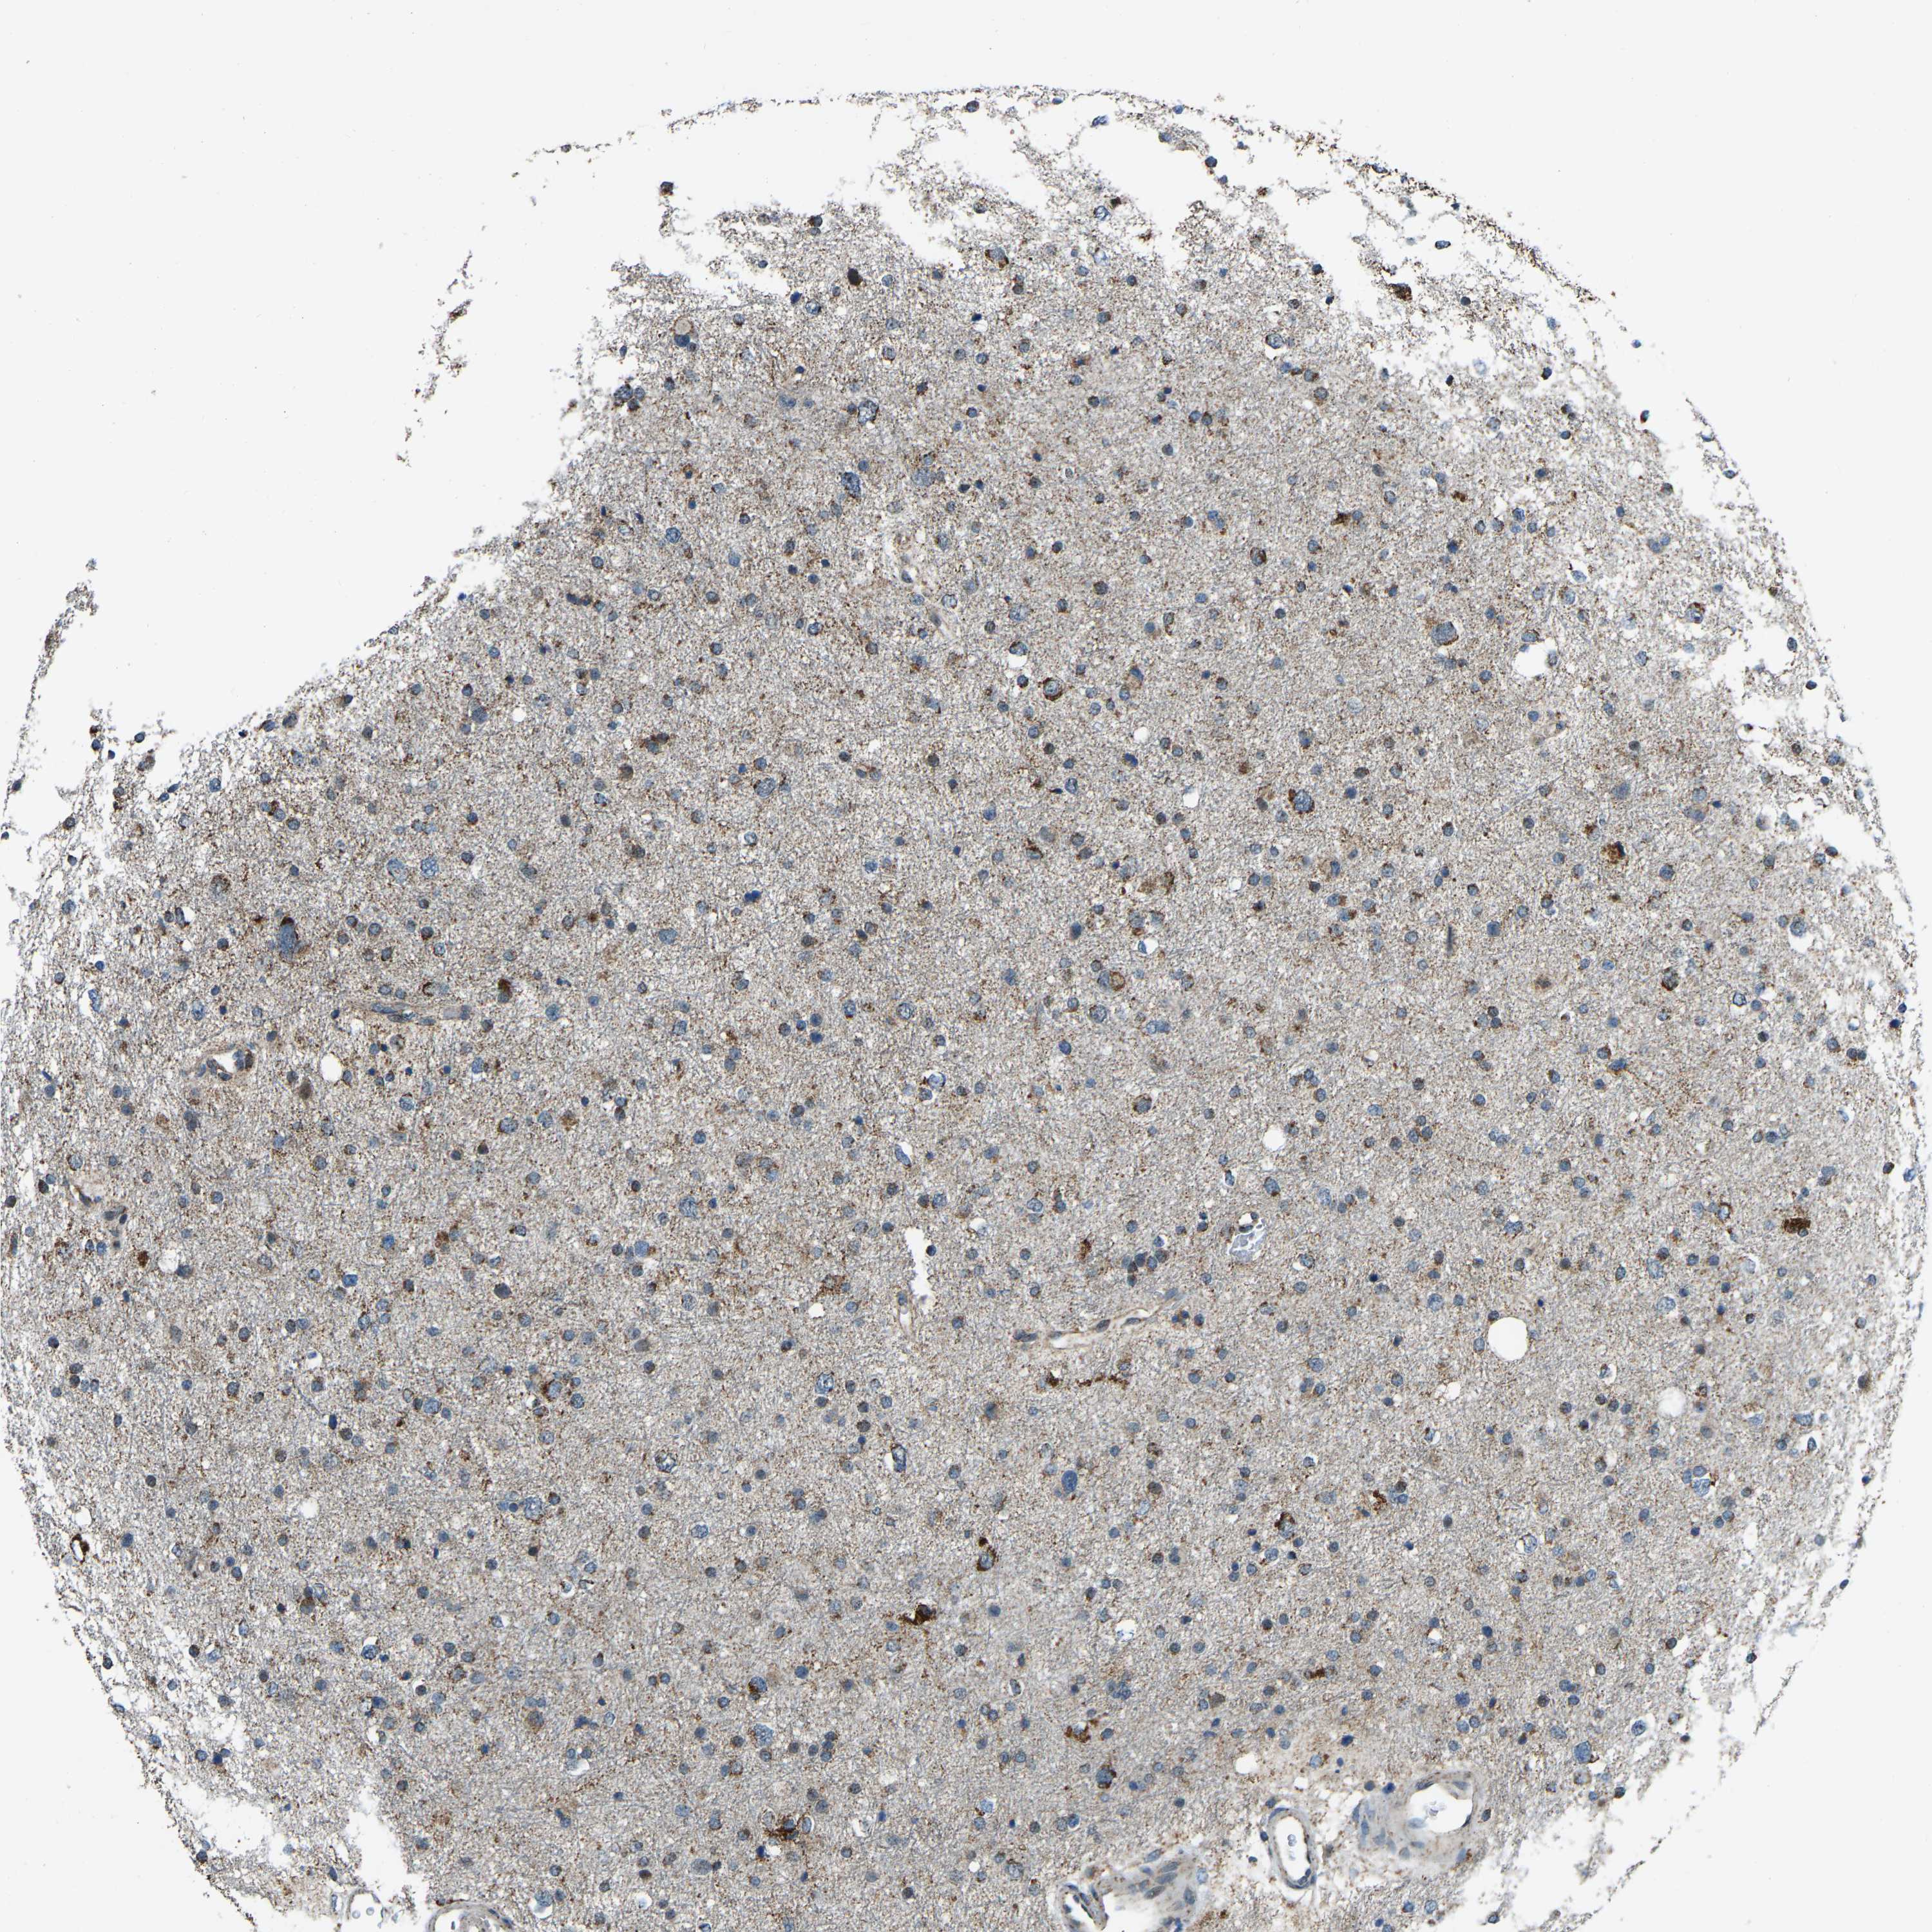

GLIOMA - Protein expressioni

A mouse-over function shows sample information and annotation data. Click on an image to view it in a full screen mode. Samples can be filtered based on level of antibody staining by selecting one or several of the following categories: high, medium, low and not detected. The assay and annotation is described here.

Note that samples used for immunohistochemistry by the Human Protein Atlas do not correspond to samples in the TCGA dataset.

Antibody stainingi

Antibody staining in the annotated cell types in the current human tissue is reported as not detected, low, medium, or high, based on conventional immunohistochemistry profiling in selected tissues. This score is based on the combination of the staining intensity and fraction of stained cells.

Each image is clickable and will lead to virtual microscopy that enables deeper exploration of all samples and also displays staining intensity scores, fraction scores and subcellular localization as well as patient and tissue information for each sample.

Antibody HPA019232

Antibody HPA021497

Antibody HPA021768

Staining

High

Medium

Low

Not detected

Intensity

Strong

Moderate

Weak

Negative

Quantity

>75%

75%-25%

<25%

None

Location

Nuclear

Cytoplasmic/membranous

Cytoplasmic/membranous,nuclear

Glioma, malignant, High grade

Glioma, malignant, Low grade